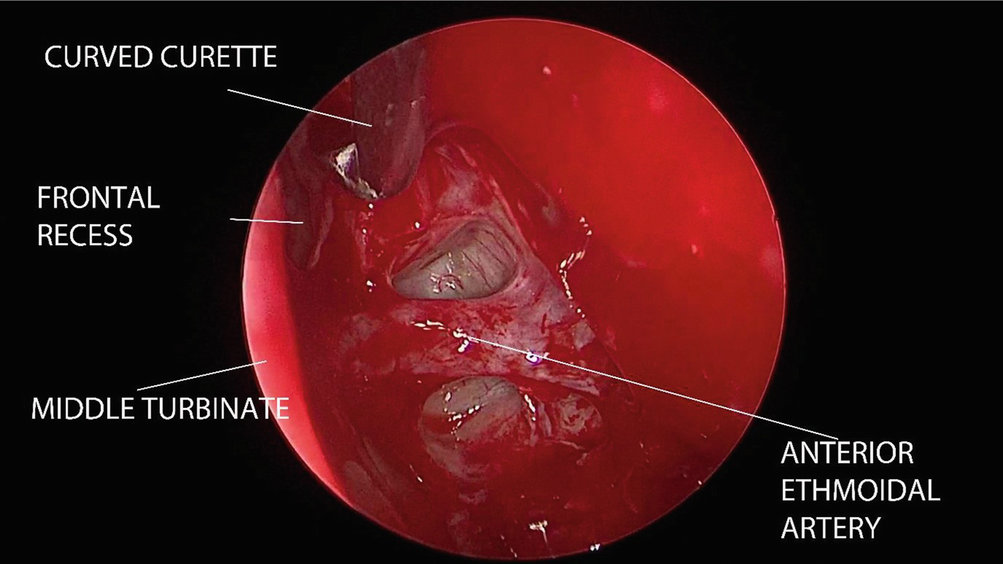

The frontal recess is opened up and cleared of disease by using a combination of a 30 or 45 degree telescope with either microinstruments or microdebrider (Fig. 12.6).

../images/481431_1_En_12_Chapter/481431_1_En_12_Fig6_HTML.png

Fig. 12.6

Frontal recess is opened up by using blunt curved curette. The anterior ethmoidal artery is located at its posteroinferior border